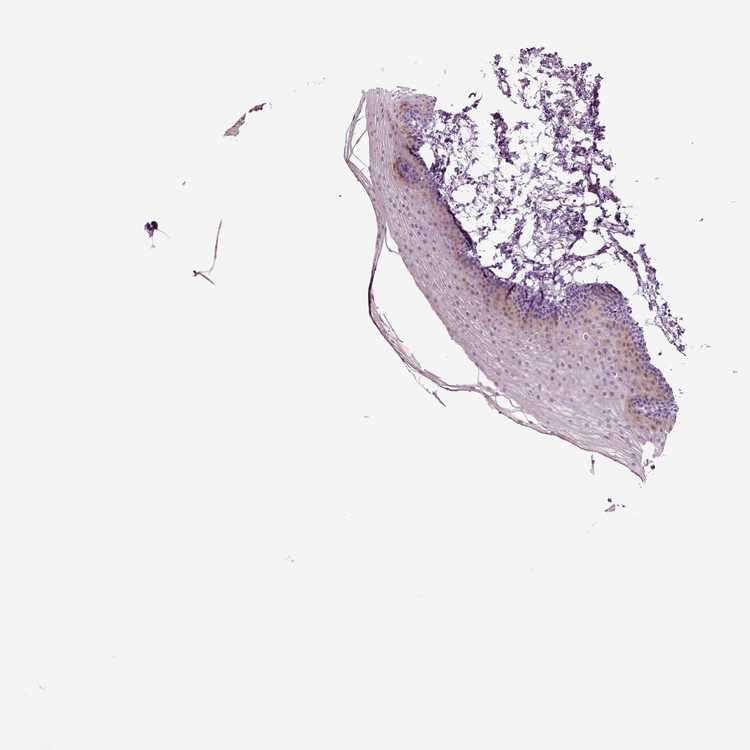

TISSUE PRIMARY DATA ORAL MUCOSA Show tissue menu

ORAL MUCOSA - Antibody stainingi

Antibody staining in the annotated cell types in the current human tissue is reported as not detected, low, medium, or high, based on conventional immunohistochemistry profiling in selected tissues. This score is based on the combination of the staining intensity and fraction of stained cells.

Each image is clickable and will lead to virtual microscopy that enables deeper exploration of all samples and also displays staining intensity scores, fraction scores and subcellular localization as well as patient and tissue information for each sample.

Antibody HPA017203

Squamous epithelial cells Not detected